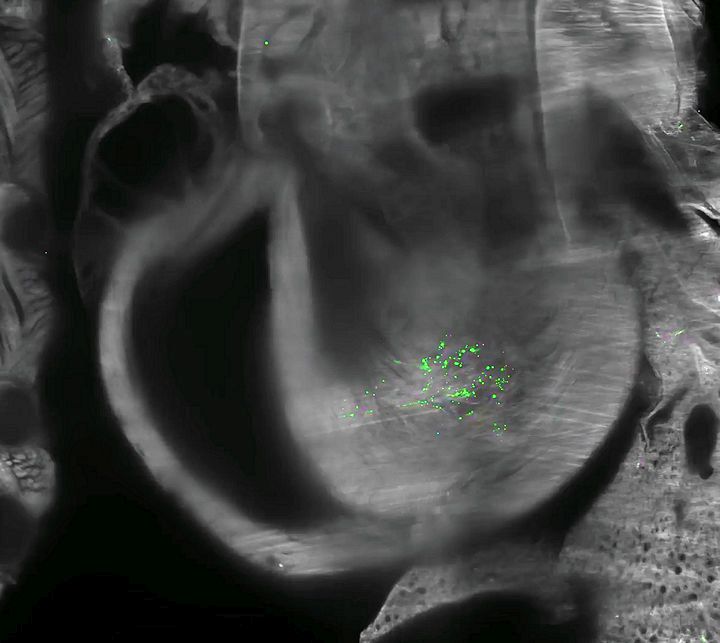

Zöld fluoreszcens fehérje (EGFP) expresszió egér szívében 72 órával kis adag, lipid nanorészecskékbe csomagolt EGFP mRNS-injekció beadása után

Luo, J., Molbay, M., Chen, Y. et al. Nanocarrier imaging at single-cell resolution across entire mouse bodies with deep learning. Nat Biotechnol (2025). https://doi.org/10.1038/s41587-024-02528-1. CC BY 4.0. 2. Videó, képernyókép

4. ábra: Lipid nanorészecskékkel bejuttatott mRNS-ből származó fehérje expressziója. Teljes test (a), lép (b), máj (c) és szív (d). f: az izomba beadott, lipid nanorészecskékkel bejuttatott mRNS-ből származó SARS-CoV-2 S1 tüskefehérje eloszlása a testben 72 órával az injekció beadása után. Tüskefehérjék a szívben (f′).

Luo, J., Molbay, M., Chen, Y. et al. Nanocarrier imaging at single-cell resolution across entire mouse bodies with deep learning. Nat Biotechnol (2025). https://doi.org/10.1038/s41587-024-02528-1. CC BY 4.0